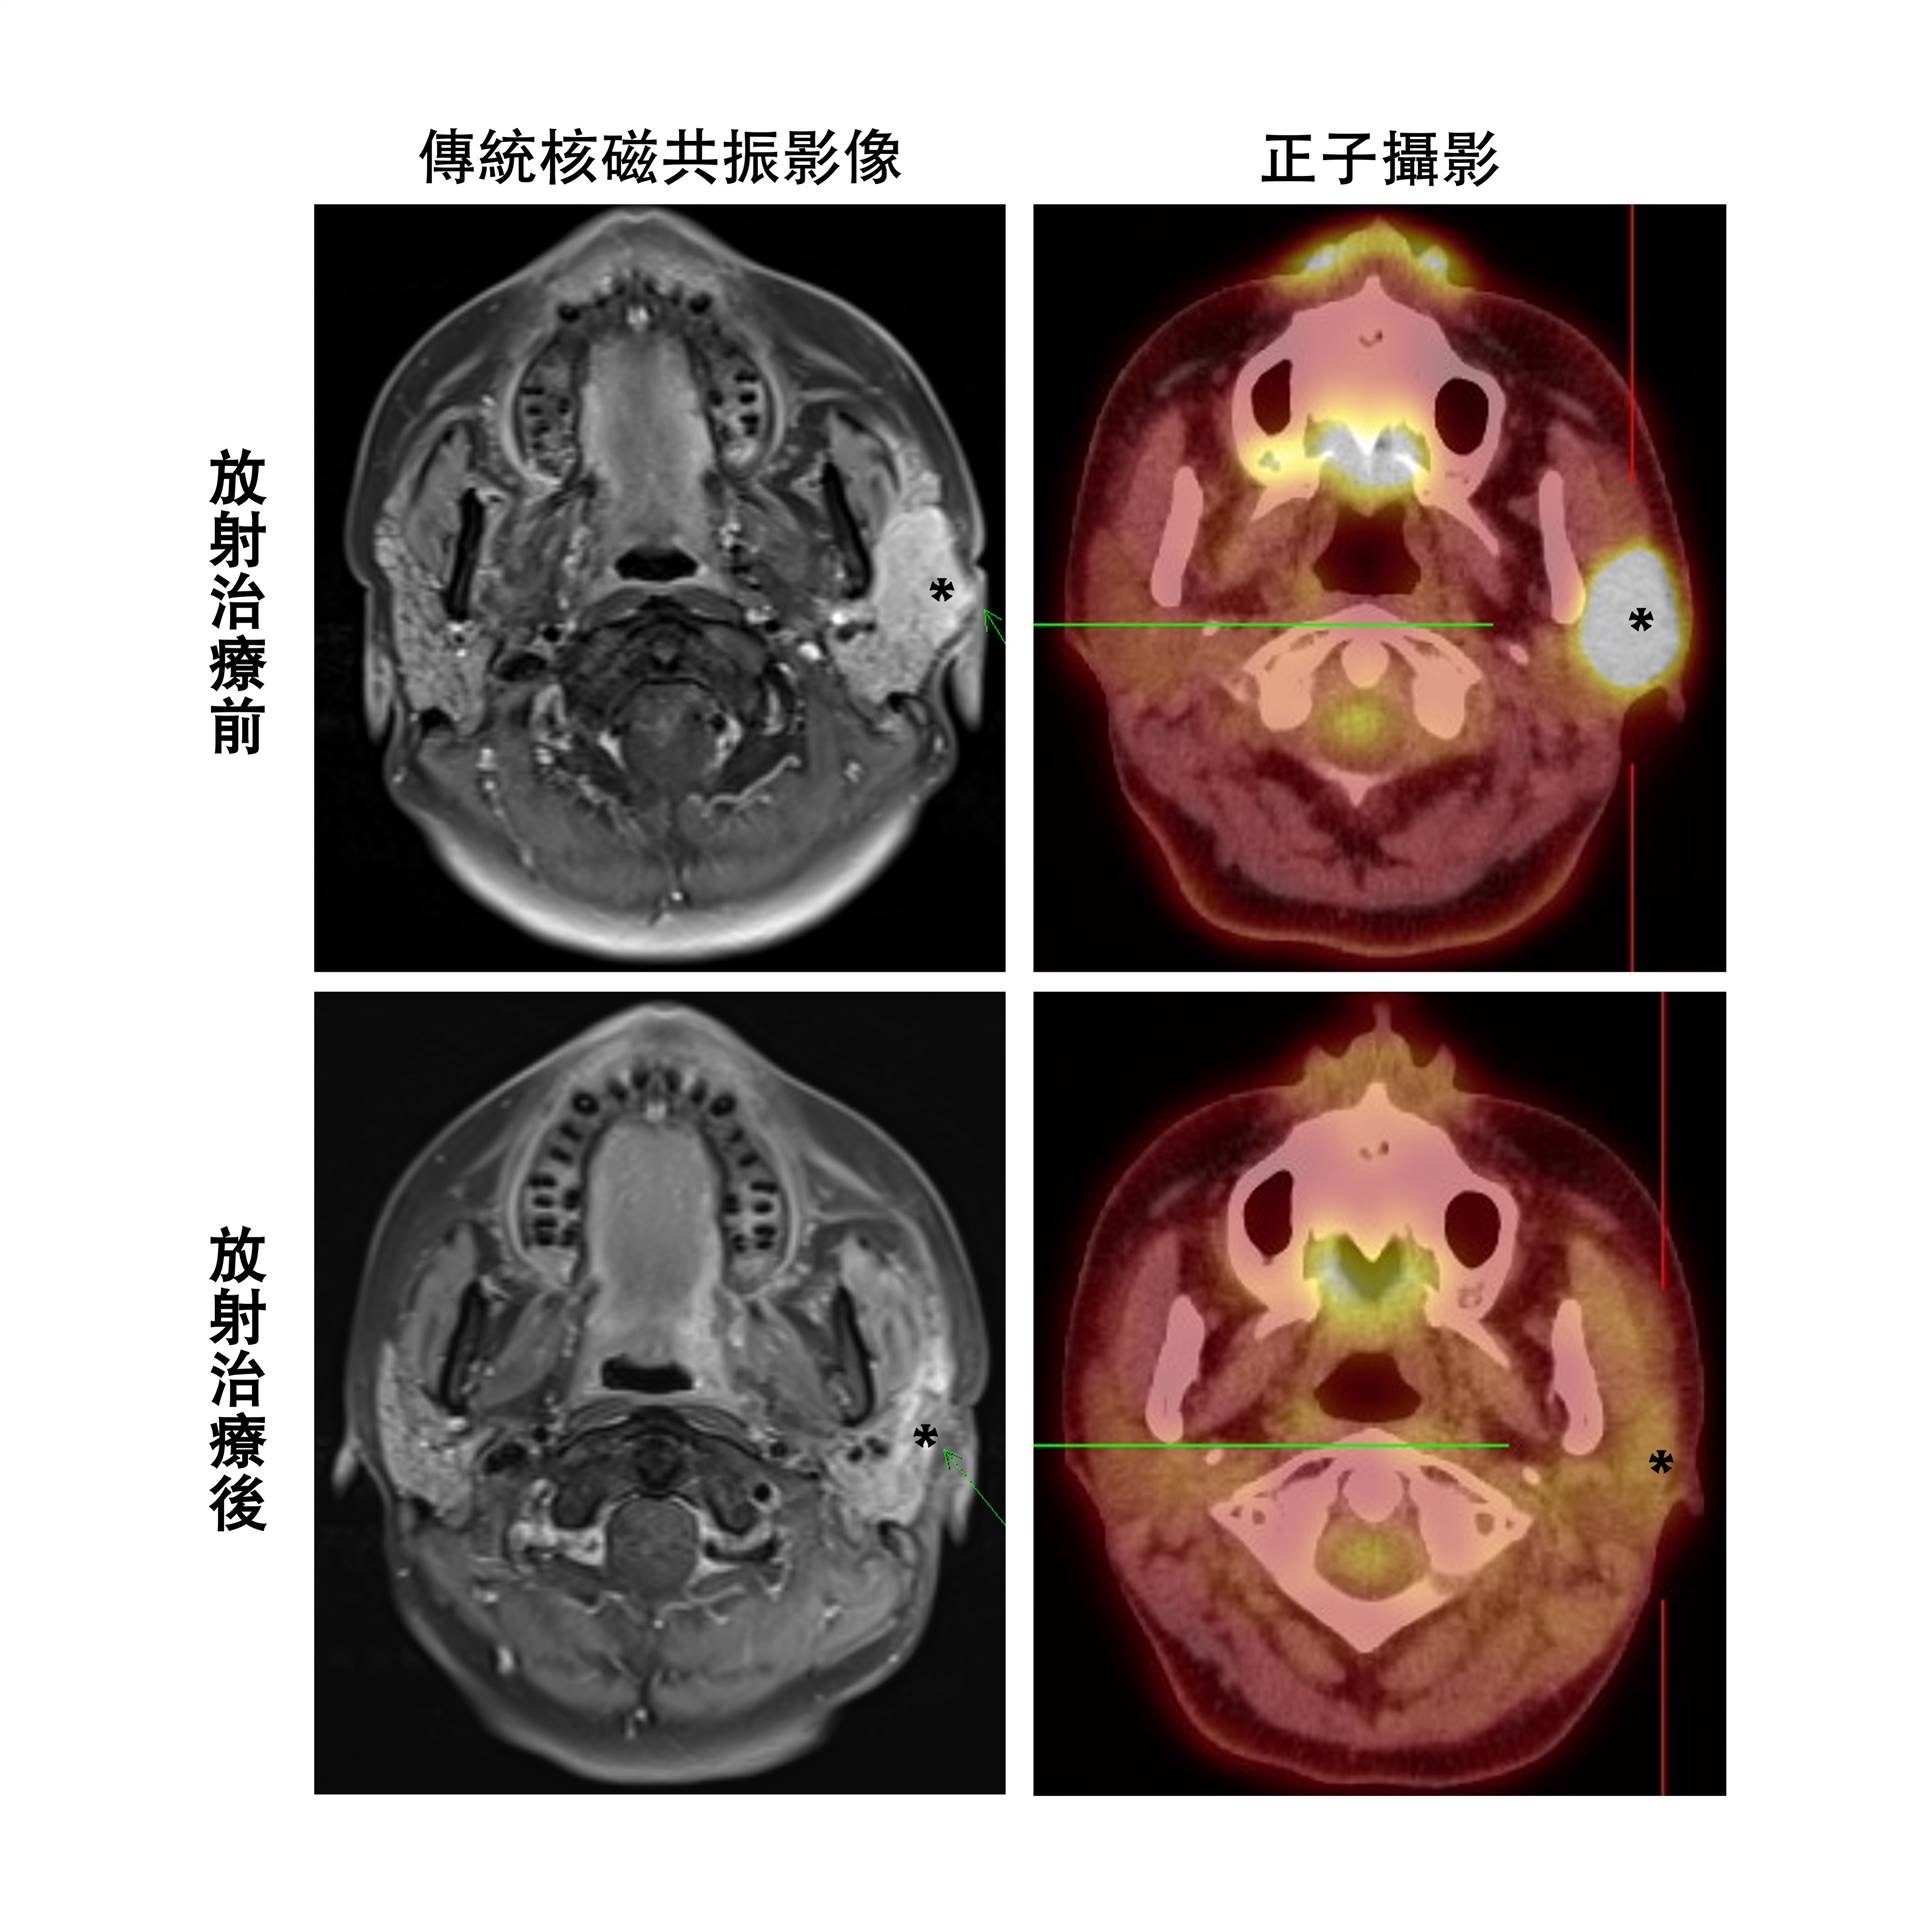

然而,由於唾液腺癌屬於生長速率較慢的癌症,患者在接受放射治療後,腫瘤明顯萎縮往往需要數個月的時間。此外,放射治療後周邊組織常會出現發炎反應,這使得傳統影像技術在判斷是否還存在殘餘腫瘤時面臨困難,也因此難以決定是否需要進一步的治療。這種不確定性往往給患者帶來極大的心理壓力,同時也增加了癌症可能進一步惡化的風險。

為解決此臨床困境,我們林口長庚醫院放射腫瘤科治療團隊,分析了林口、基隆、高雄及嘉義長庚四個院區共115位接受放射線治療的唾液腺癌病患,展開為期五年以上的追蹤、觀察與分析。研究結果顯示,葡萄糖正子攝影對於評估唾液腺癌患者放射治療效果的準確性高達85%,顯著優於傳統電腦斷層或核磁共振影像約60%的準確率。

這項研究發現,葡萄糖正子攝影能更有效檢測出放療後殘存腫瘤的情形,並能更早識別出放射治療效果不佳的患者,從而及時介入輔助性化學治療或手術切除殘餘病灶,以期提高疾病控制的機會。

正子攝影作為一種非侵入性、快速且安全的檢查方式,能夠及早評估治療效果,從而協助臨床醫師制定個人化的精準醫療策略。對於放射治療效果良好的病患,正子攝影有助於避免不必要的後續醫療介入,進而減少由過度治療可能引起的顏面缺損、吞嚥困難、神經損傷等副作用風險。